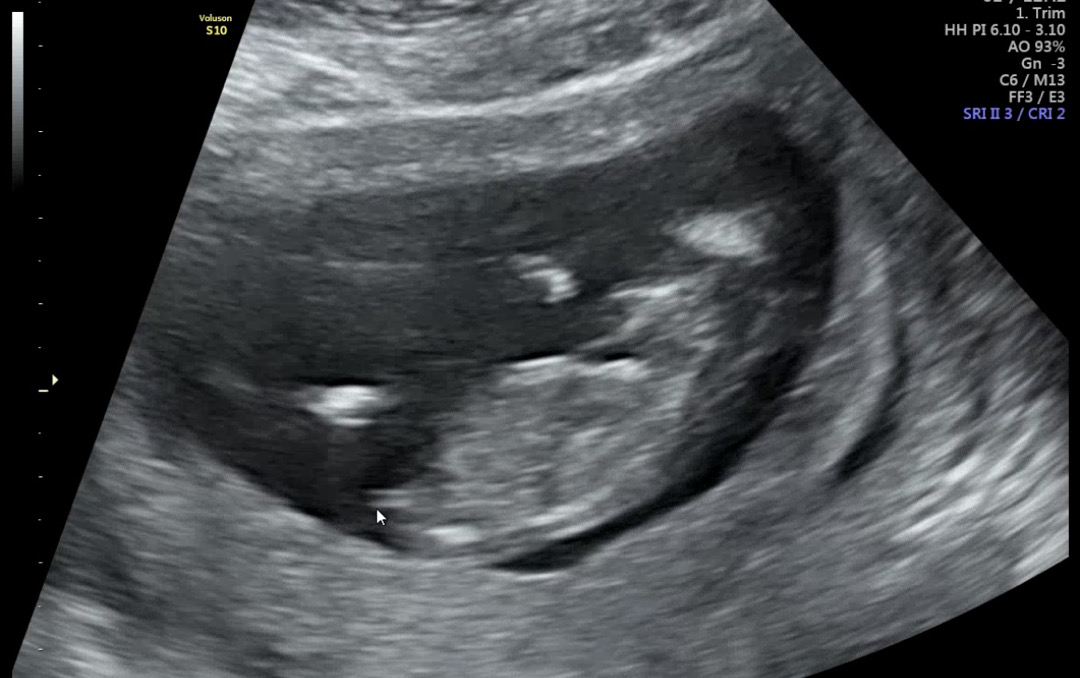

12주 2일차 각도법 너무 궁금해요!!!

딸일까요 아들일까요? ㅎㅎㅎ

딸같아용